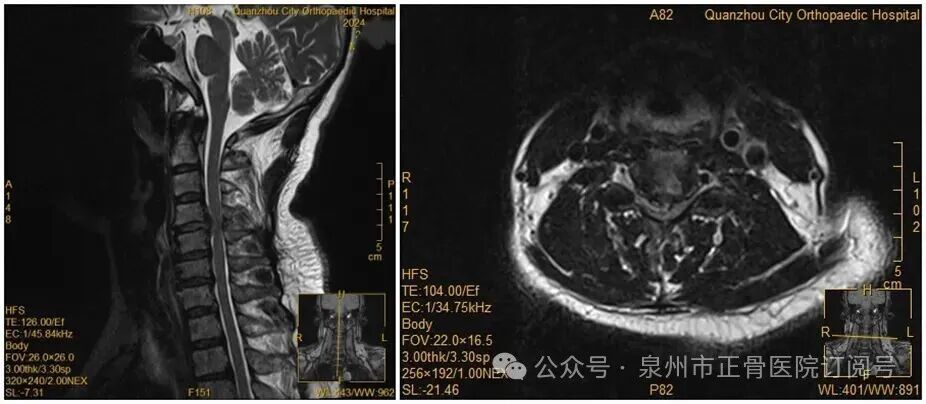

王女士术前MRI

虽然已经出现了瘫痪,王女士仍然惧怕手术,不愿意接受手术。经过医务团队及王女士家人耐心解释及劝解后,王女士才愿意接受手术治疗。医院为王女士紧急实施手术。手术顺利,经过一段时间恢复,她的肢体功能逐渐回归正常。